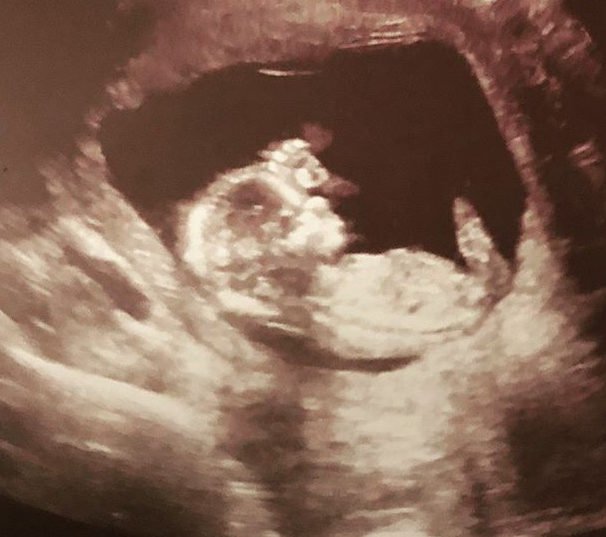

15 Haftalık Gebelik Ultrason Görüntüleri

15 Haftalık Gebelik. Gebelikte 15 hafta bebeğinizin gelişmesi hızla devam eder. Ultrasondan bakınca nefes alış verişi dudak hareketleri gözlenebilmektedir. Bebeğiniz yaklaşık 50 gr, yüz hatları belirginleşmeye devam etmektedir ve büyük bir zamanı uyku ile geçmektedir. Gebelikte 15.hafta bulantılar genellikle yerini açlık.